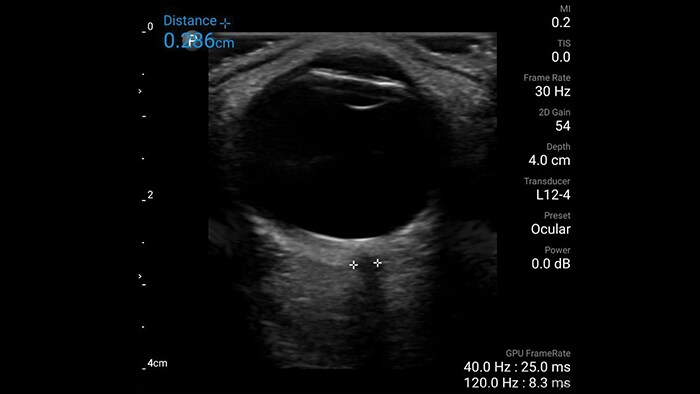

Evaluate trauma or perform a quick in-office scan to visualize and assess anatomical detail and blood flow within the eye and its surrounding structure, including quantitative measurements.